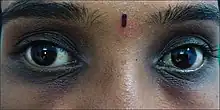

| Woman with hereditary dark circles | |

Periorbital hyperpigmentation, also known as hereditary dark circles, is characterized by darker skin around the eyes caused by the presence of additional melanin. It is an extremely common hereditary human characteristic and is frequently found on individuals with dark skin. Periorbital hyperpigmentation is most prevalent within the 16–25 age group.[1]